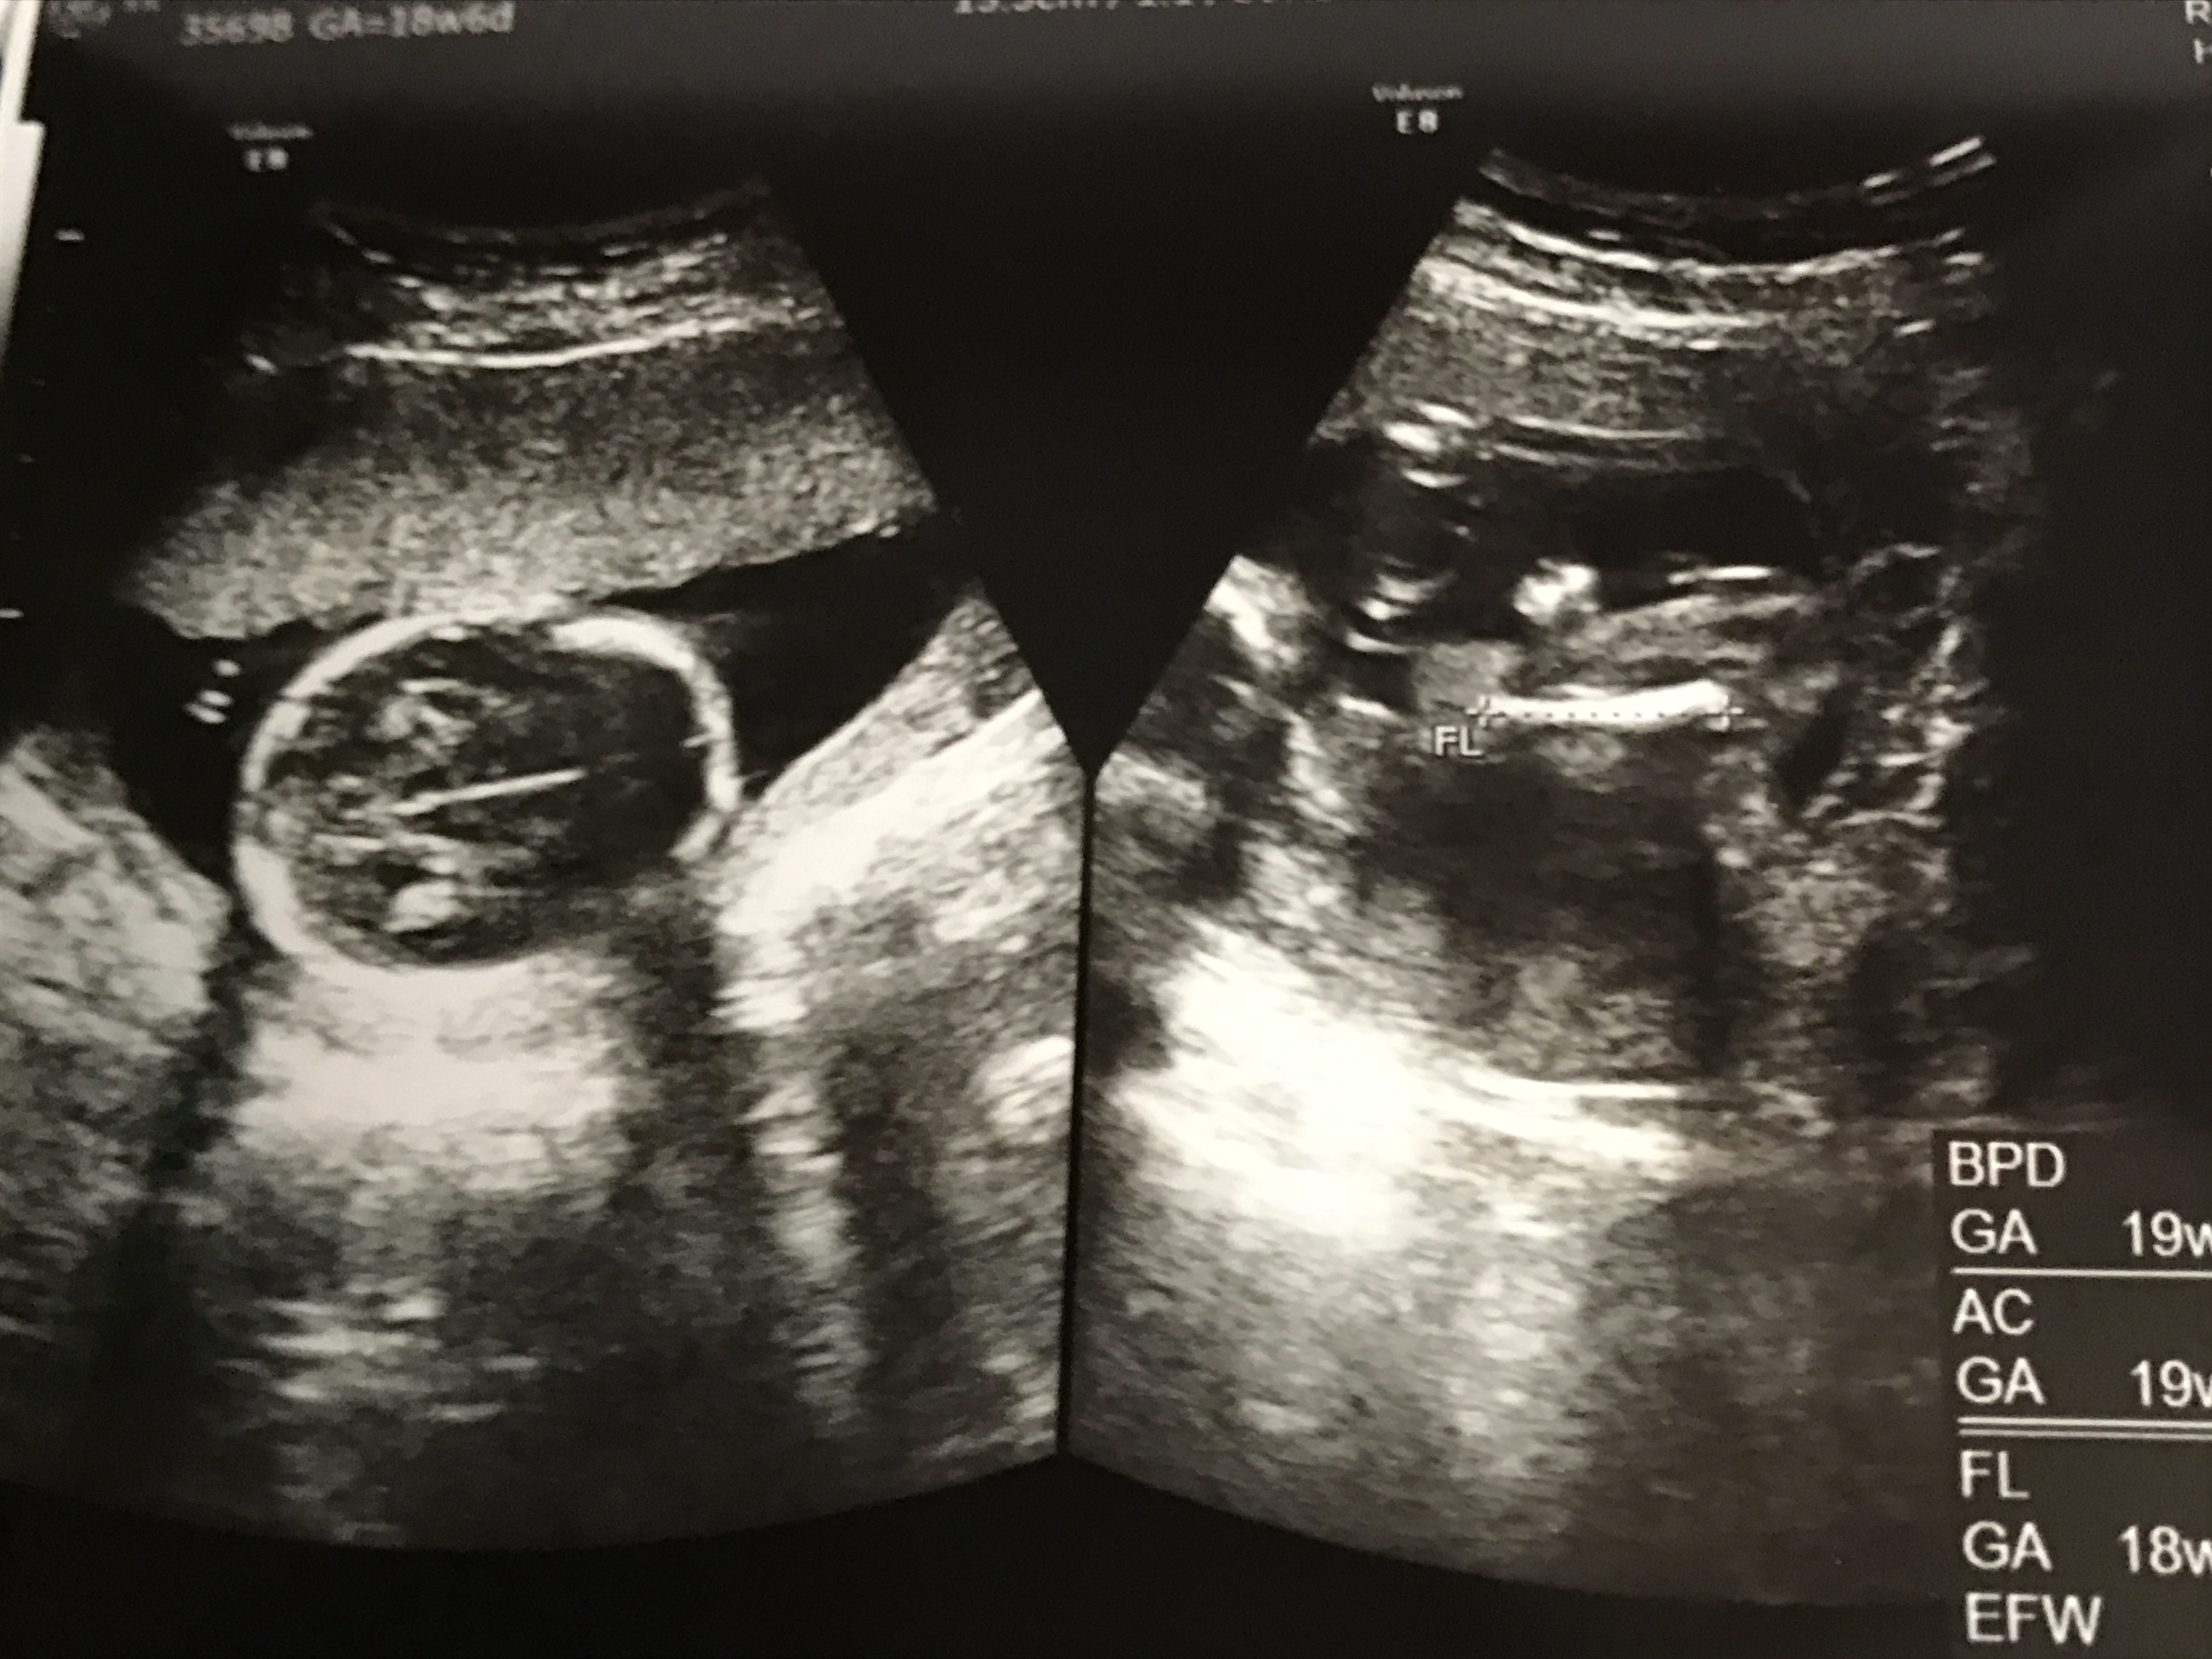

医師監修 妊娠19週のエコー写真を多数掲載 みんなのエピソードつき マイナビウーマン子育て

妊娠週目エコー写真 胎児の大きさや胎動の様子 性別 妊娠中期 All About